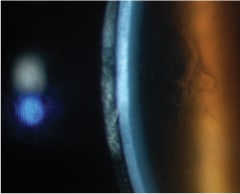

Figure 2 was taken one week later after the patient had worn redesigned LDS lenses for about three hours. Blanching of the conjunctival vessels and chemosis are prominent.

Figure 2. A redesigned large-diameter scleral lens resulted in blanching of conjunctival vessels and chemosis.

Figure 3 was taken upon removal of the redesigned LDS lenses from Figure 2. The analysis was that the cornea and conjunctiva were not typical of ocular GVHD. The corneal clinic prescribed oral anti-viral medications.

Figure 3. Appearance of cornea following removal of redesigned lenses from Figure 2. Oral anti-viral medications were prescribed.